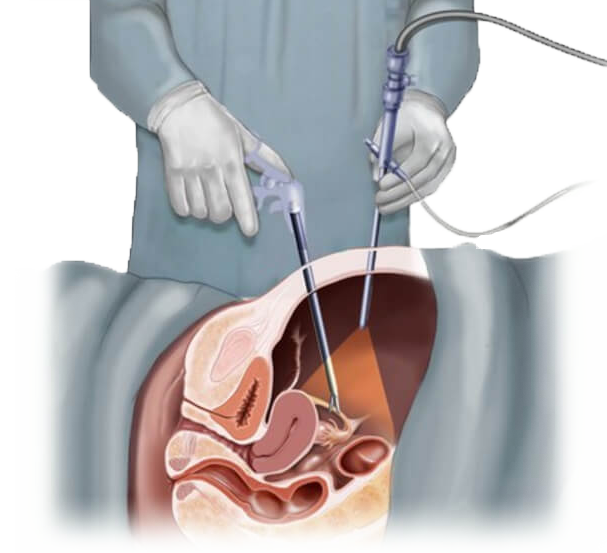

Современные методы лапаротомии и миомэктомии